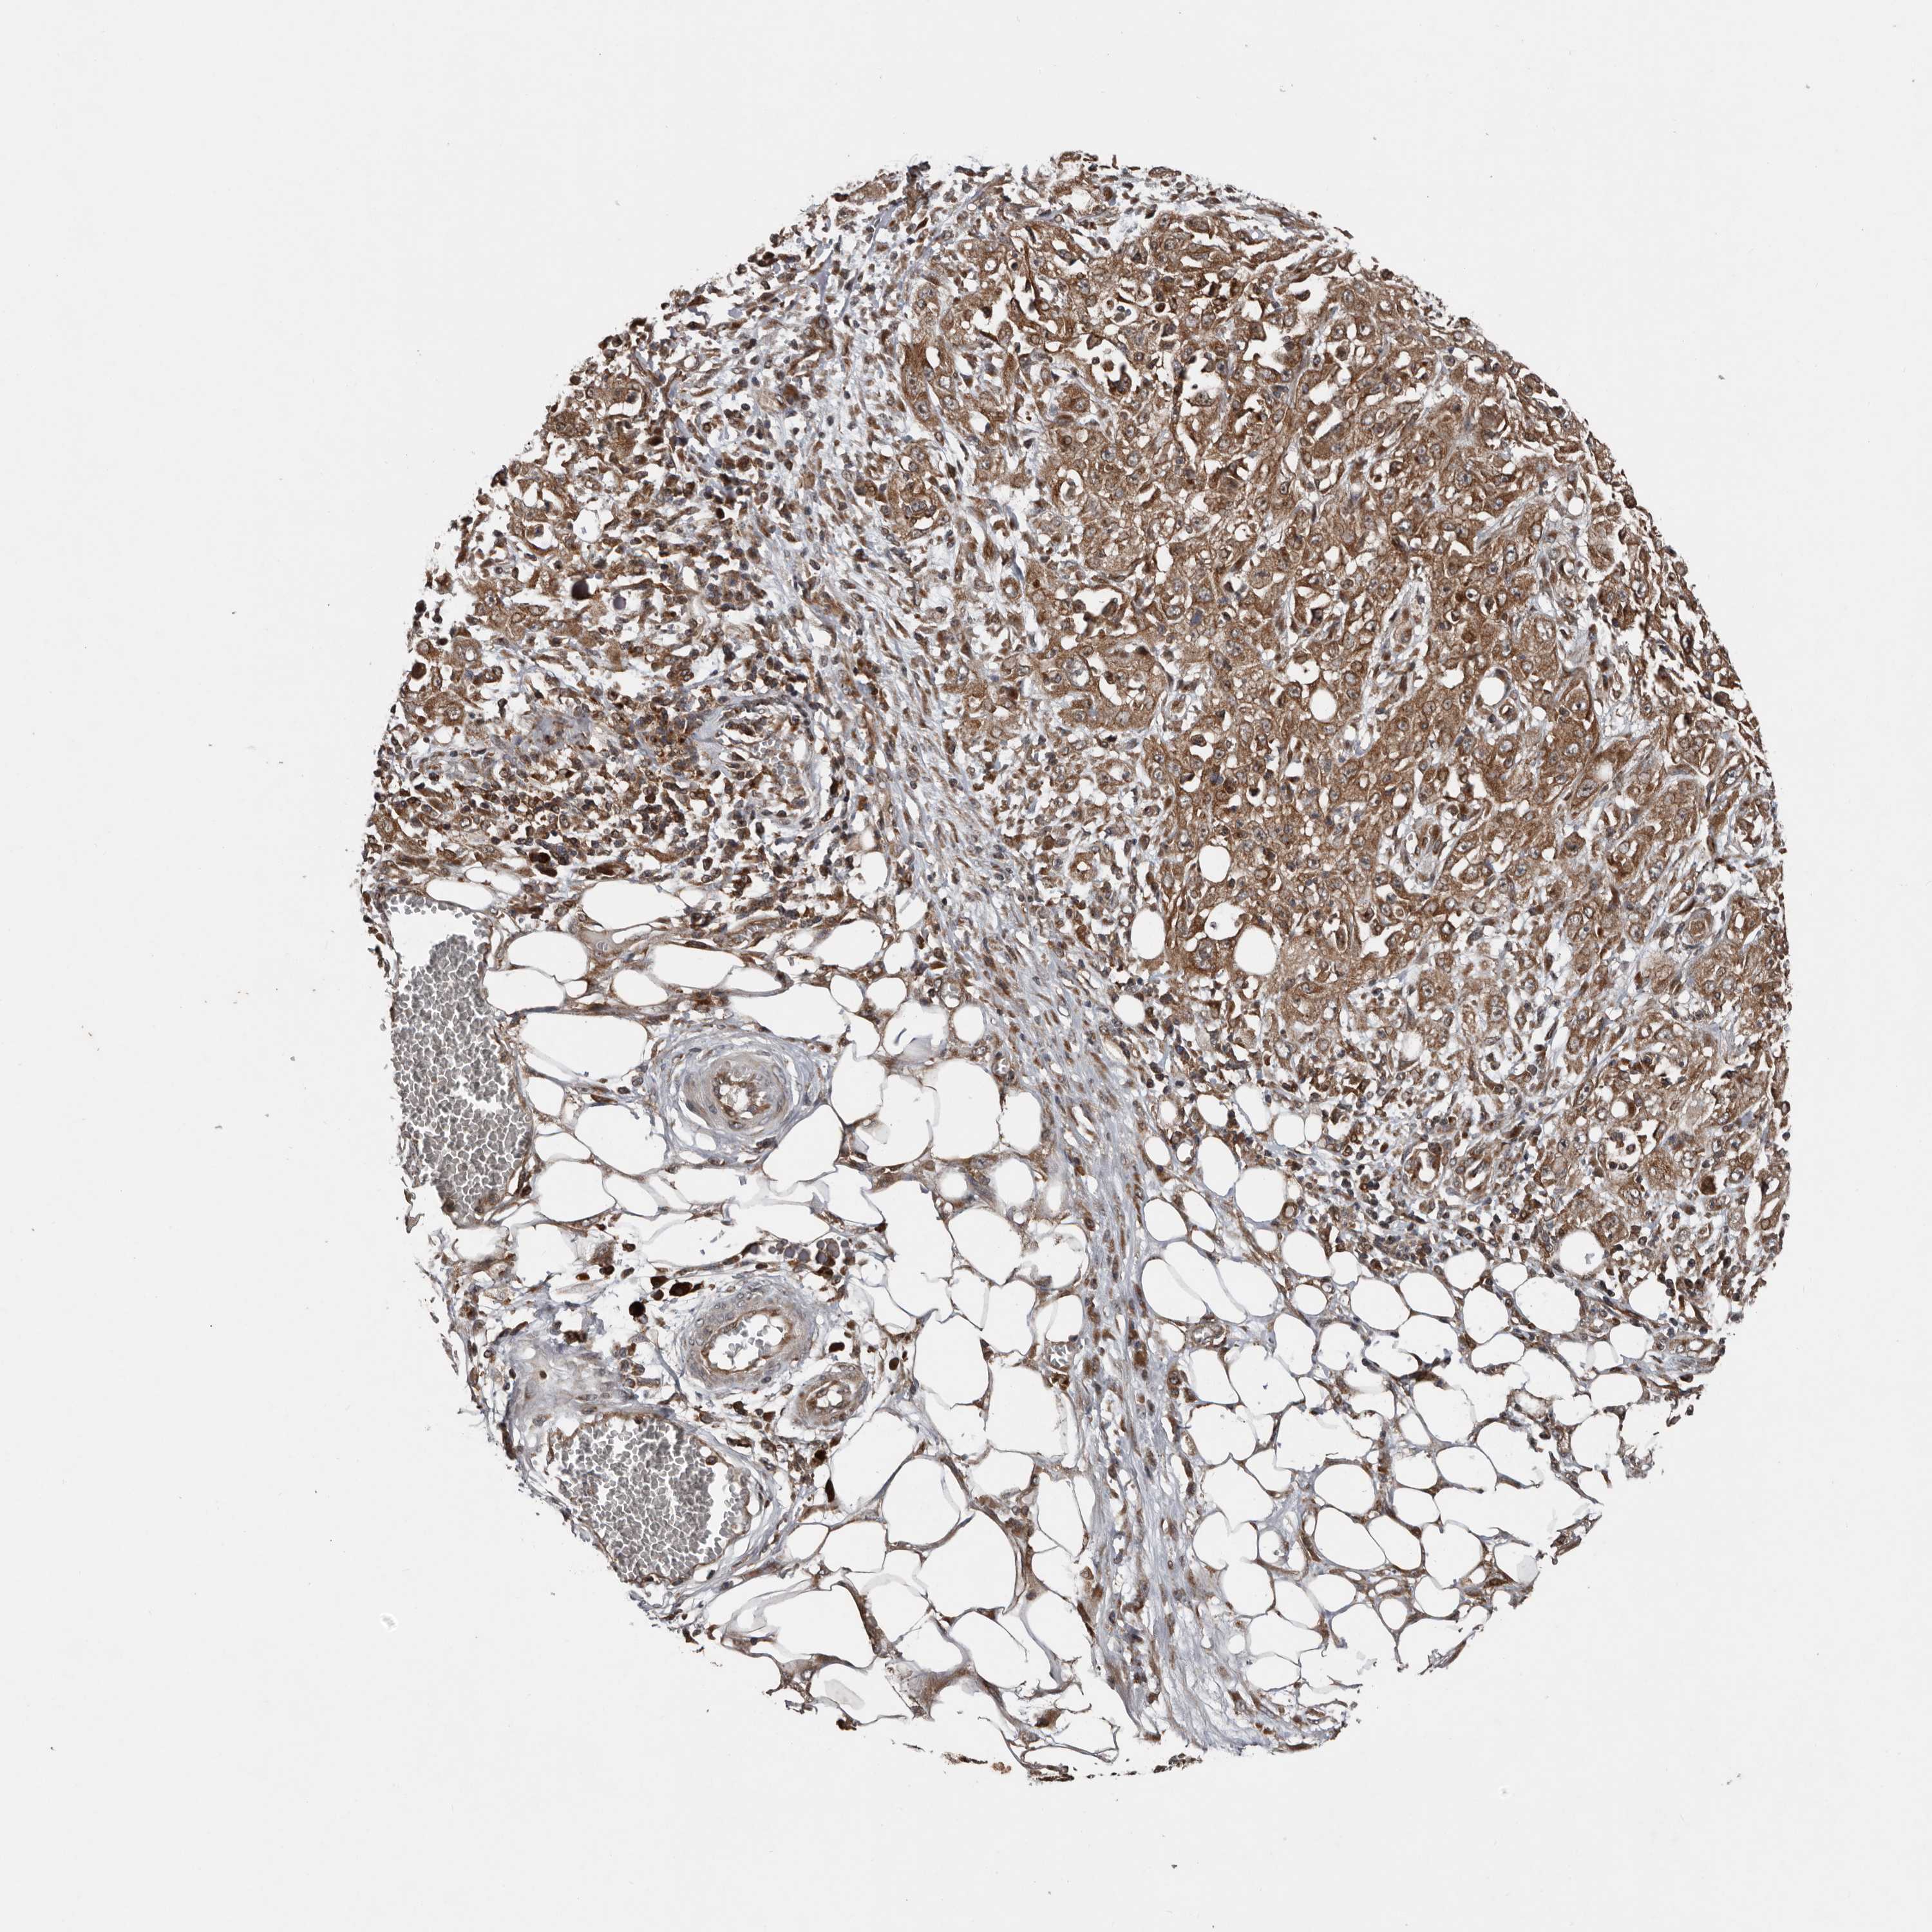

SKIN CANCER - Protein expressioni

A mouse-over function shows sample information and annotation data. Click on an image to view it in a full screen mode. Samples can be filtered based on level of antibody staining by selecting one or several of the following categories: high, medium, low and not detected. The assay and annotation is described here.

Each image is clickable and will lead to virtual microscopy that enables deeper exploration of all samples and also displays staining intensity scores, fraction scores and subcellular localization as well as patient and tissue information for each sample.

Antibody HPA028579

Basal cell carcinoma